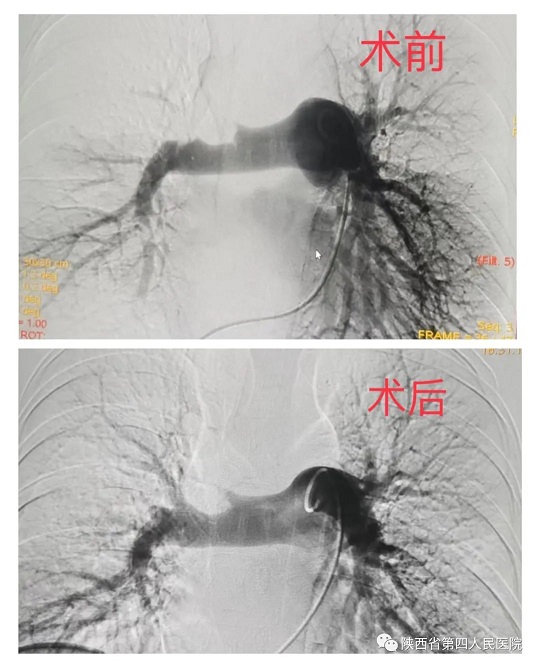

近日,我院卒中中心成功救治一名双侧颈内动脉闭塞、脑动脉多发狭窄、后交通开放并部分代偿供血患者。70岁患者……

近日,我院心血管内科专家团队成功救治了一名突发急性肺栓塞的患者。经充分评估病情后,为患者行急诊手术,通过医护人员准确、及时的救治后,患者转危为安。患者,年轻女性,37岁,因外伤骨折术后卧床40余天,活动后出现胸闷、胸痛、气短,及一过性意识障碍,家……